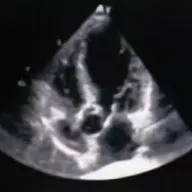

术前超声

超声提示:主动脉瓣右冠瓣脱垂,主动脉瓣中-重度关闭不全,左心系统扩大,二尖瓣少量反流。